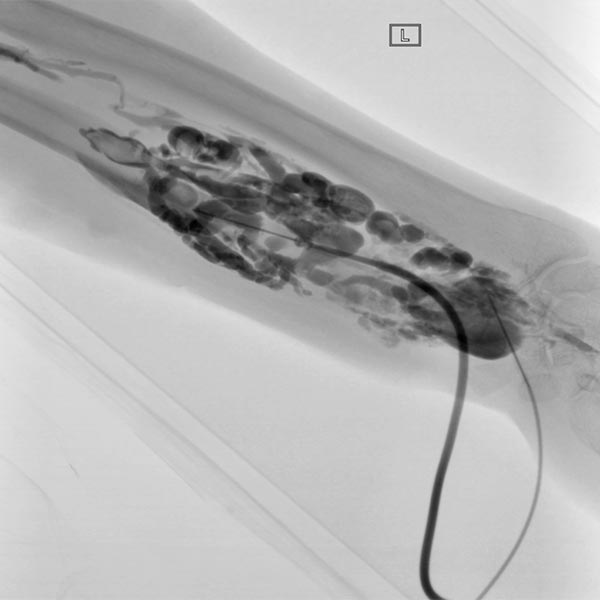

A total of seven sessions of sclerotherapy were performed, in which the venous malformation was sclerosed using polidocanol 3% (up to 4 ml per session). During this procedure, the perfused portions of the malformation are directly punctured with a 21G needle under ultrasound guidance. After aspiration of venous blood, contrast injection is performed to assess the distribution, or rather the communications of the individual malformation portions with draining outflow veins. This is followed by slow injection of foamed polidocanol, followed by elastic compression bandaging for 24 h.